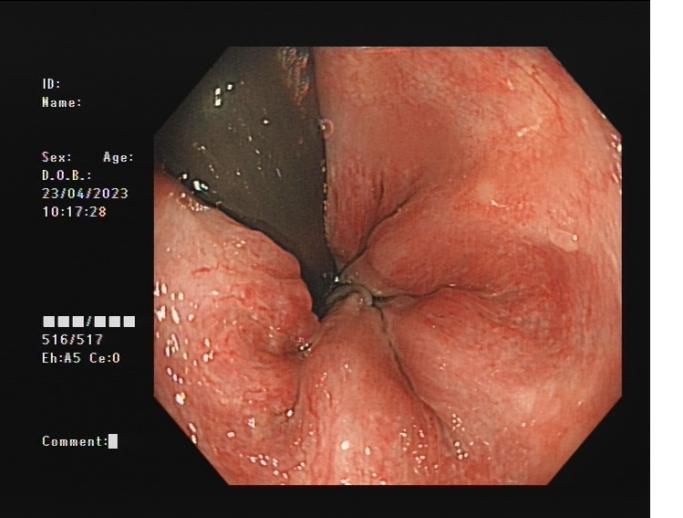

內痔 內鏡下內痔硬化治療

內鏡下內痔硬化術:治療I-Ⅲ度內痔伴有內痔相關癥狀;I~Ⅲ級內痔飲食及藥物治療無效;內痔手術后復發,肛門反復手術后不能再次手術;恐懼外科手術,不愿意接受手術治療;高齡、高血壓、糖尿病和嚴重的系統性疾病,不能耐受外科手術等。